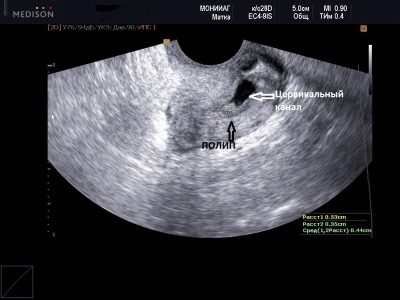

Полип

Доброкачественный нарост возникает из околоплодных оболочек и часто проникает в полость влагалища. Небольшие полипы не представляют угрозы для здоровья как будущей матери, так и ребенка. Однако более крупные образования могут вызвать осложнения во время родов или привести к незначительным кровотечениям из влагалища. Если полип поврежден, в слизистых выделениях могут появиться отдельные светло-красные полоски.

Наибольшую опасность представляют полипы, возникшие до беременности. При отсутствии своевременного лечения и постоянном травмировании они могут перерасти в онкологические заболевания шейки матки. Удаление доброкачественного нароста во время беременности проводится крайне редко, только если существует риск преждевременного раскрытия шейки матки. Операцию по удалению полипа назначают женщинам начиная с семнадцатой недели после зачатия.